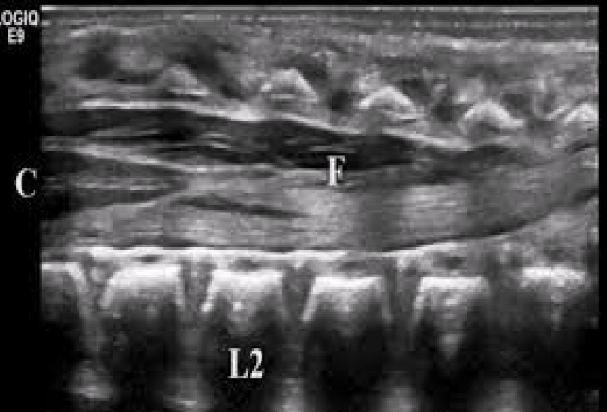

f

filum terminale

c

conus medullaris

a

anterior and posterior margins of spinal cord

b

echogenic nerve roots in the subarachnoid space